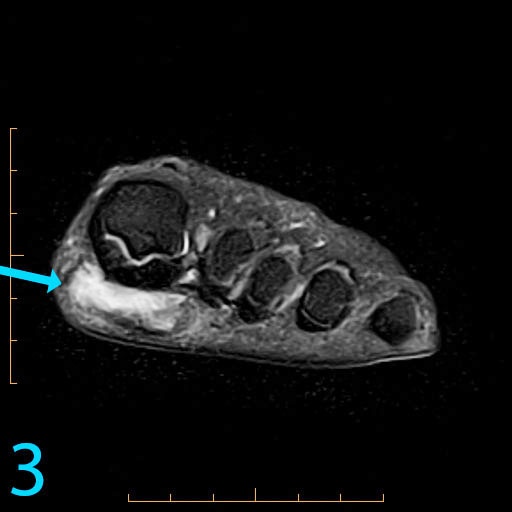

This 18-year-old female presents with a palpable soft tissue mass subjacent to the first metatarsophalangeal (MP) joint that she has noticed for 1-2 months. It is painful with shoes and ambulation, and you are evaluating her for a soft tissue tumor. What is the cause of her problem, and what pertinent negatives must you notice?

This patient has a so-called "pressure lesion" due to ambulation, with associated adventitial bursa/pseudobursa formation within. It is a chronic process. This is manifested as a large, ovoid mass-like structure within the subcutaneous soft tissues along the plantar aspect of the first MP joint and sesamoid bones (arrow). It is well-circumscribed and demonstrates a mildly lobulated configuration. There is peripheral signal hypointensity indicating a rim or rind of fibrosis, and there is intermediate to high T2 signal centrally, suggesting a component of complex fluid. The major differential diagnosis is fibroma of tendon sheath. This is a counterintuitive diagnosis as fibrous lesions are typically dark on all pulsing sequences. But, fluid signal from the tendon sheath may be found in this specific fibrous tumor. So, fibromas of tendon sheath are typically hyperintense centrally.

While the lobulation of the lesion medially is reminiscent of plantar fibromatosis, the constellation of findings remains most compatible with a giant pressure lesion. Fibromatosis (non-aggressive type) occurs more proximally in the middle aponeurotic cord of the plantar fascia. The findings are not suspicious of an aggressive neoplastic lesion (based on location and concentric shape), and you can also rule out MP joint capsulitis and Morton's neuroma because of location. You should always rule out plantar plate tear along the second MP joint on thin section sagittals if you have a large pressure lesion under the second metatarsal head. For more case review, visit MRI Online.